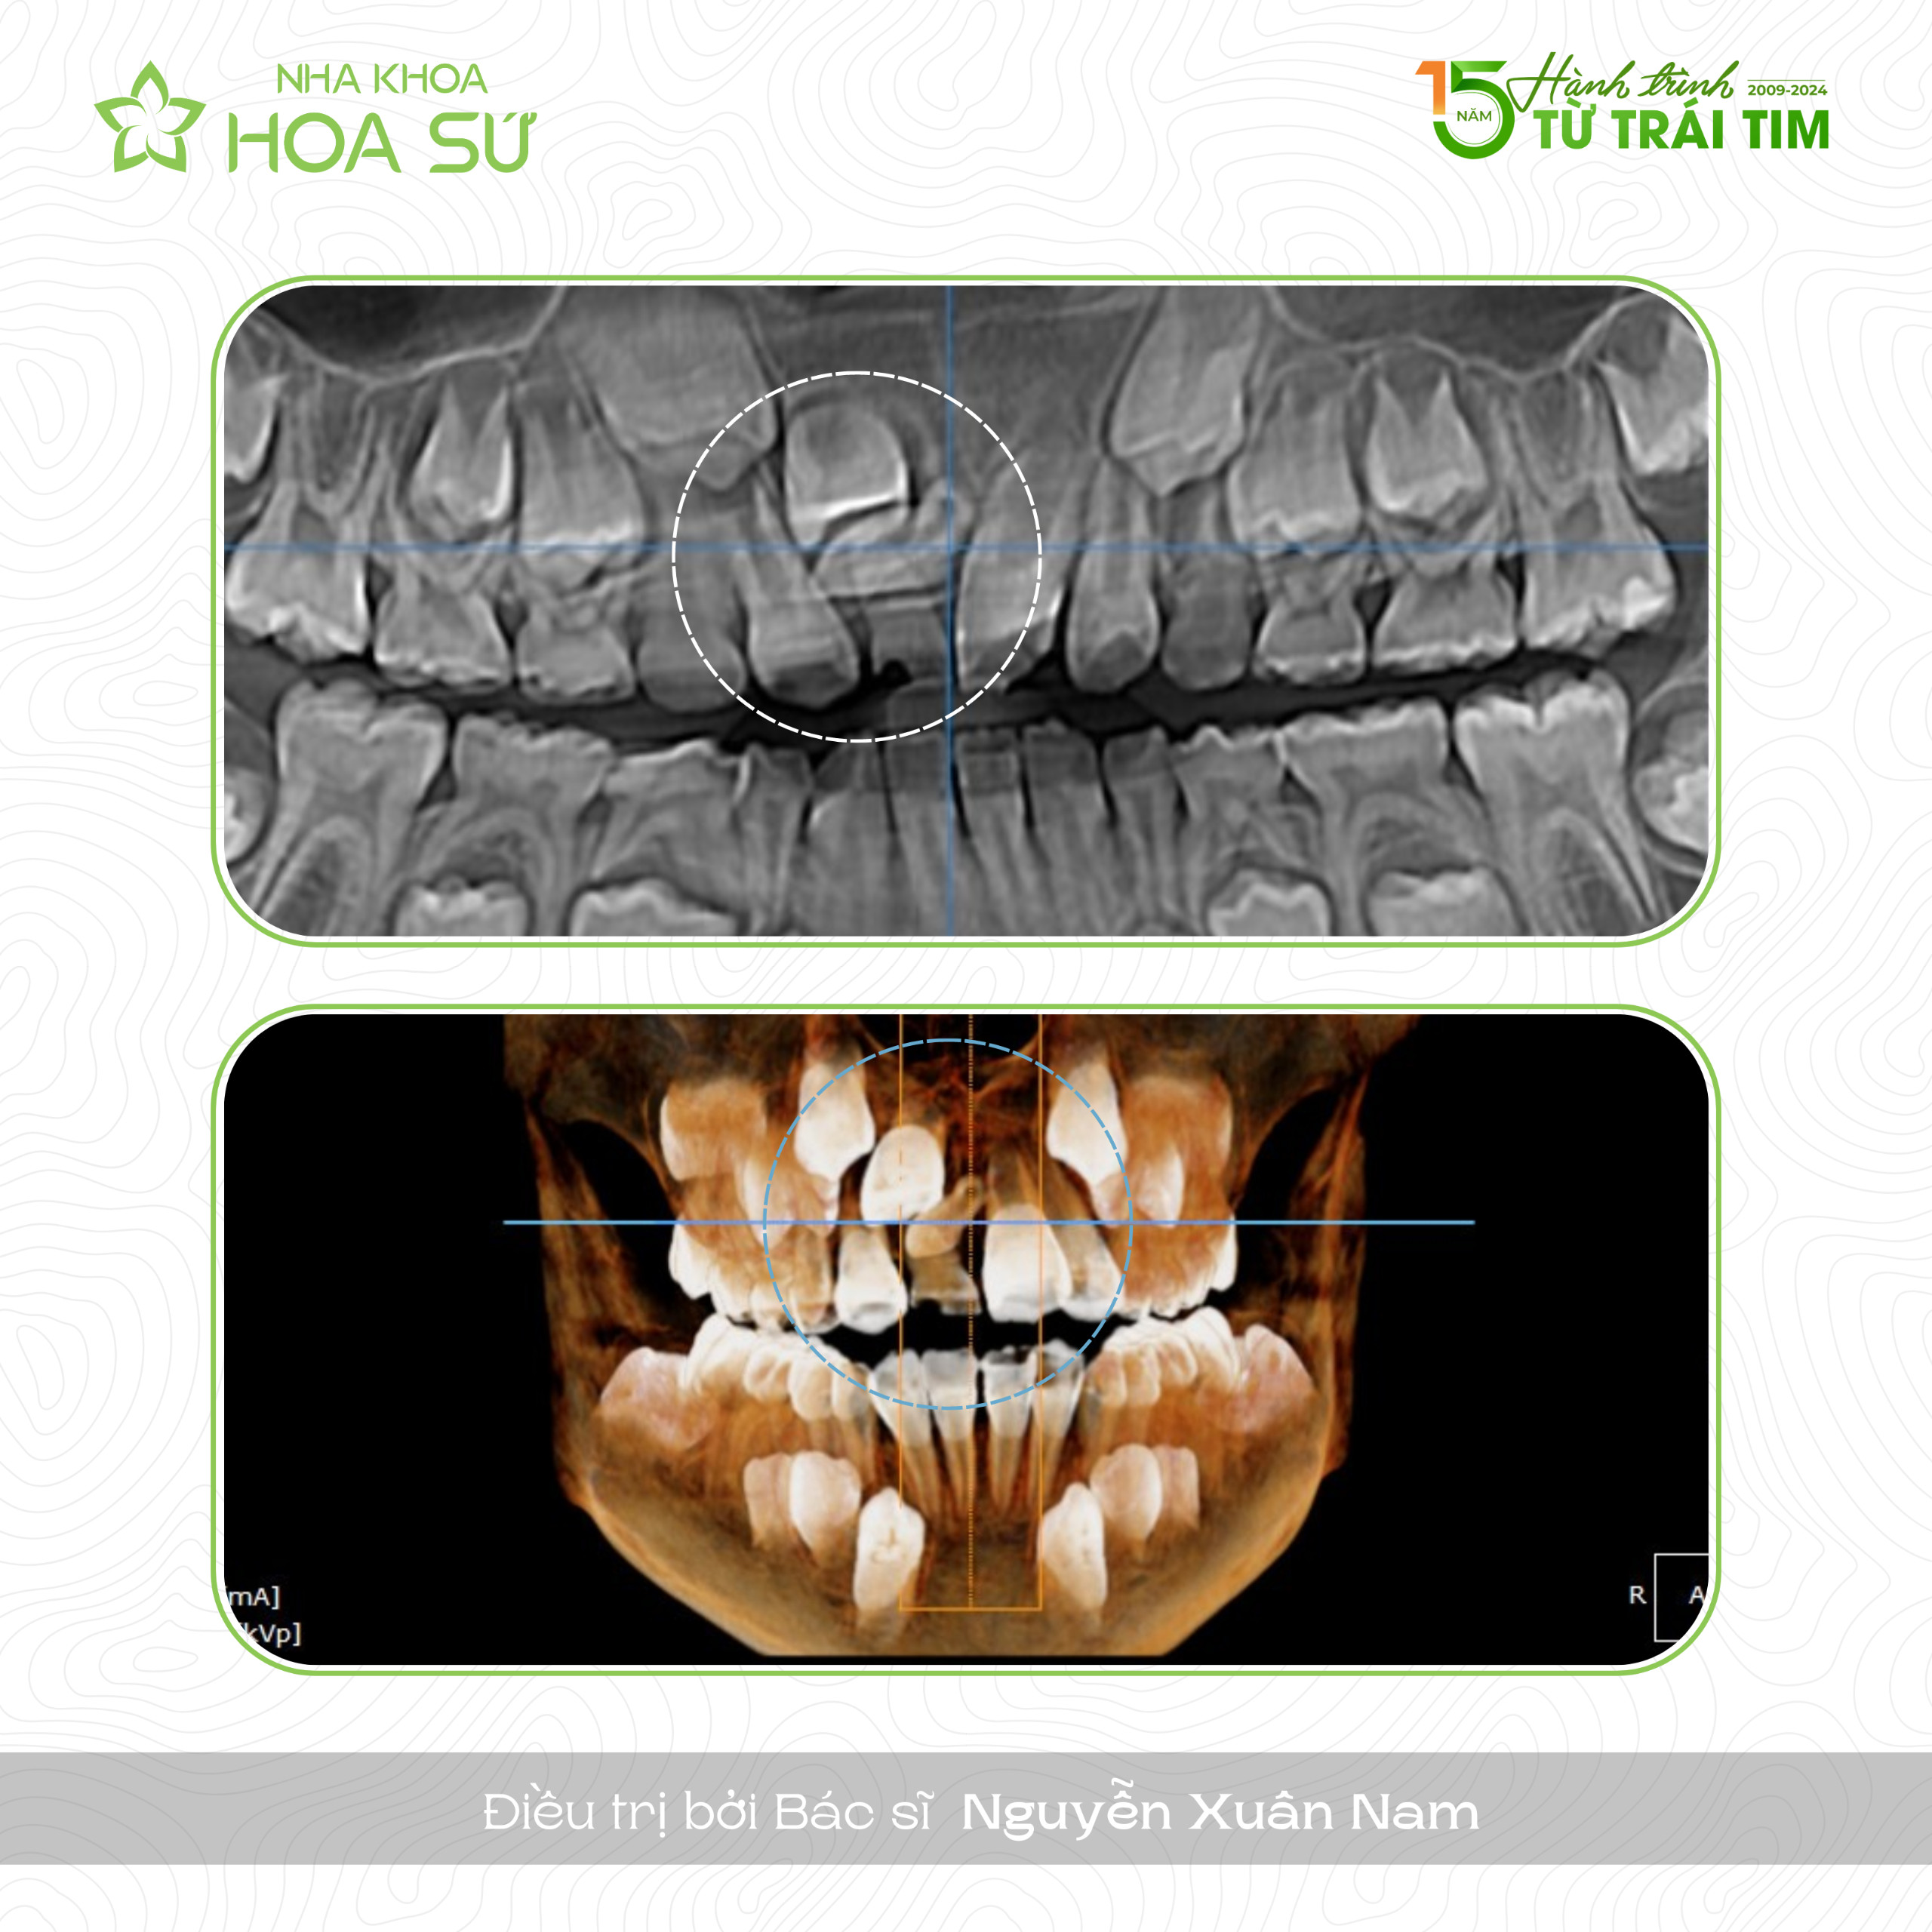

0b6d4ed944e3eabdb3f2 Đã xuất bản Tháng 4 22, 2024 lúc 2560 × 2560 trong RĂNG DƯ KẼ GIỮA LÀ TÌNH TRẠNG NHƯ THẾ NÀO ⁉ ← Trước Tiếp theo →